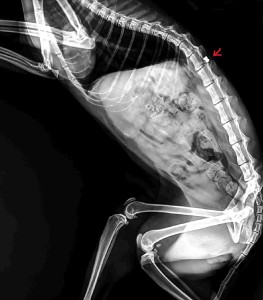

Střelná poranění u koček

Na zde vložených fotografiích je prezentováno několik rentgenových snímků letošních pacientů,u kterých bylo náhodně diagnostikováno střelné poranění,třeba i několik let staré.Co to asi naznačuje o našem celospolečenském vztahu ke zvířatům posuďte sami.